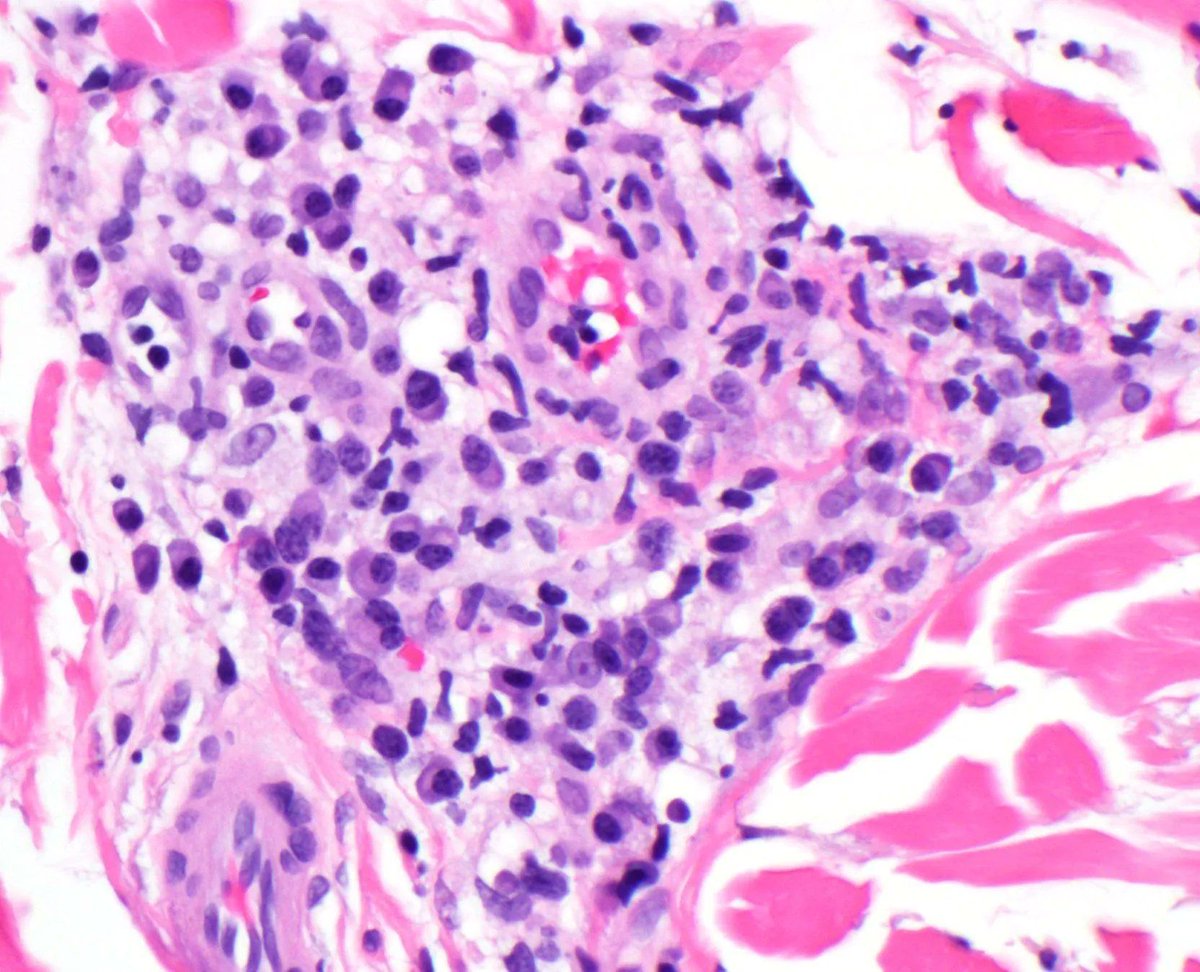

LANGERHANS CELL SARCOMA: Rare tumor of dendritic family often in dermis/subcutis. Sheets of bizarre pleomorphic/epithelioid cells. Rare dx not to forget about! (+) Langerin, S100, CD1a. #bstpath Jerad Gardner, MD @histiocytosisX Steven Billings, MD Scott Lauer, MD Rajiv M. Patel, M.D.